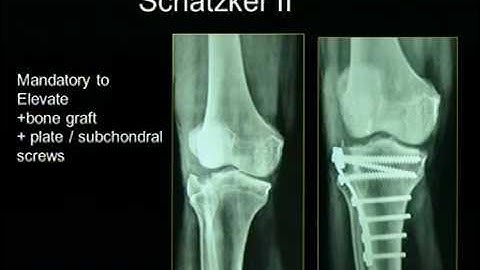

Proximal Tibia Plating System